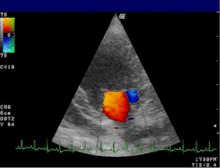

Цветовое допплеровское картирование (ЦДК)[править | править исходный текст]Основано на кодировании в цвете значения допплеровского сдвига излучаемой частоты. Методика обеспечивает прямую визуализацию потоков крови в сердце и в относительно крупных сосудах. Красный цвет соответствует потоку, идущему в сторону датчика, синий — от датчика. Темные оттенки этих цветов соответствуют низким скоростям, светлые оттенки — высоким. Недостаток: невозможность получения изображения мелких кровеносных сосудов с маленькой скоростью кровотока. Достоинства: позволяет оценивать как морфологическое состояние сосудов, так и состояние кровотока по ним. 13bf68840df13b79f5dd075294c4e1d7.gif

Валюш я с таким же диагнозом как и ты  big_smiles_127.gif поэтому тебя очень понимаю.  Это там на верху последнюю ступеньку к счастью  с препятствиями для тебя придумали.  Иногда надо отпустить ситуацию, на всё забить, иначе лопнет голова. Давай по порядку. Мужик твой не успевает переваривать инфу от тебя, если проще то он в ахуе, мужики они такие. Так что если он хоть какие то шажочки делает, это уже для него подвиг, уже не отказал. Про доплер я тебе писала, доплер называеться процедура, где смотрят кровоток матки и плода, а так как ты пока не беременна , кровоток матки у небеременных смотрят по УЗИ с ЦДК, врачи это и объясняют доплер это кровоток мать- ребёнок. А мы ж тут бля на ББ профессора медицины. Так что на УЗИ с ЦДК запишись, кровоток сосудов  матки это,  Квоту переделать, это даёться время твоему Орлу в сознание прийти, чтоб всё осознанно было и с желанием.  Ну а про паспорт, да просто день не тот.  Валюш всё будет ХОРОШО, поверь, потом посьмеёмся над этими шалостями тех с верху  girl.gif

Валюш это точно, мчиш. Узи с ЦДК не везде делают. УЗИ женских половых органов ТВ датчиком с ЦДК сосудов яичников, эндометрия, миометрия - метод диагностики, с помощью которого можно обнаружить структурные изменения малого таза у женщины, а также оценить состояние кровотока по основным сосудам малого таза посредством цветового допплеровского кодирования (ЦДК).Цветовое доплеровское картирование  в гинекологии  -  исследование гемодинамических показателей матки и яичников в течение менструального цикла. Результаты исследований допплерометрических показателей  отражают циклические изменения, соответствующие полноценному овариоменструальному циклу и   помогают диагностировать не только органическую но и функциональную патологию женской репродуктивной системы.   Валь что то я не поняла на какой день цикла надо делать Я на 21ДЦ записалась